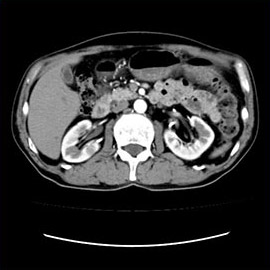

80列マルチスライスCTで撮影した画像

腹部

腹部(造影)